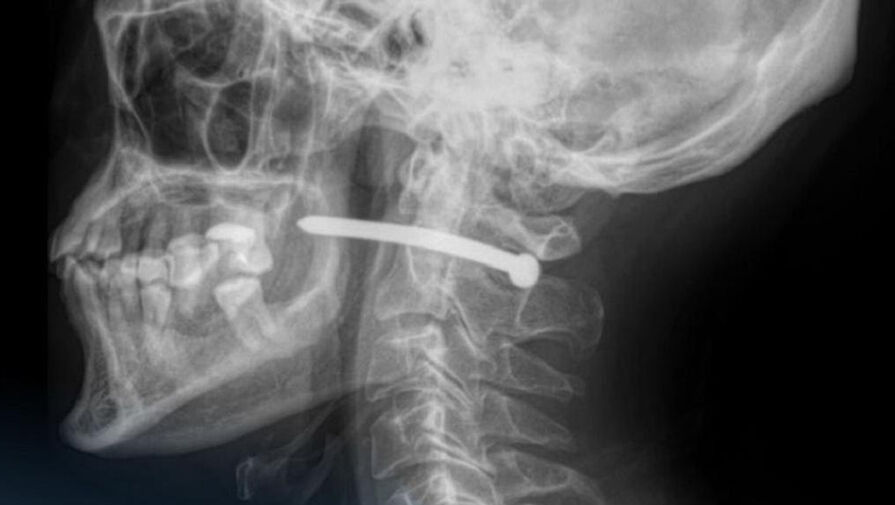

В Петропавловске 51-летний мужчина обратился в городскую больницу скорой помощи с ранением за ухом. Как выяснилось, во время ремонта он случайно получил травму — в него выстрелил гвоздь из пневматического пистолета.

Рентген показал, что металлический предмет прошел буквально в миллиметрах от шейного отдела позвоночника. Медики отметили, что мужчине невероятно повезло — жизненно важные органы и сосуды не были повреждены.